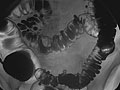

The colon is filled with a contrast material that contains barium so that the colon can be seen on an X-ray. This is done by pouring the contrast material through a tube inserted into the anus. The barium blocks X-rays, causing the barium-filled colon to show up clearly on the X-ray picture.

• If a double-contrast study is being done, the barium will be drained out and your colon will be filled with air.

• In a single-contrast study, the colon is filled with barium. This outlines the intestine and shows large abnormalities.

• In a double-contrast or air-contrast study, the colon is first filled with barium, and then the barium is drained out. This leaves only a thin layer of barium on the wall of the colon. The colon is then filled with air. This provides a detailed view of the inner surface of the colon. It makes it easier to see narrowed areas (strictures), diverticula, and swelling.